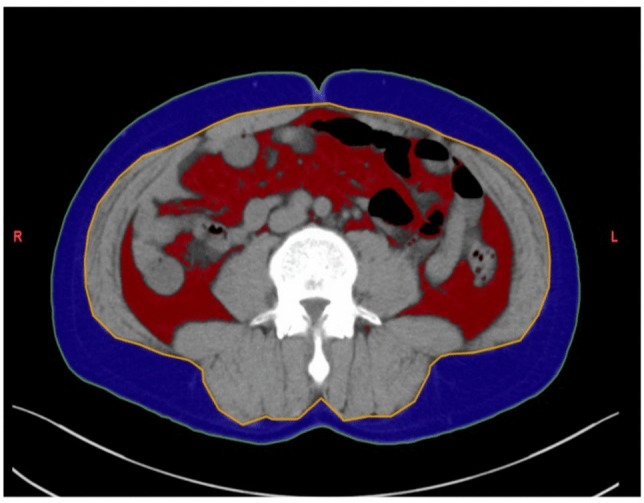

Methods: We prospectively enrolled patients with UC scheduled for two-stage restorative proctocolectomy with a preoperative plan for hand-sewn IPAA. Patients were categorized into a conversion group that required conversion to stapled IPAA intraoperatively and a non-conversion group. Preoperative visceral fat area and anatomical indicators were measured using computed tomography (CT). Logistic regression analysis was performed to identify predictors of conversion surgery.

Results: A total of 106 patients were included, with 12 (11.3%) in the conversion group. Compared with those in the non-conversion group, patients in the conversion group had significantly higher body mass index (BMI), greater visceral fat, and a longer distance between the ileal end and the anal verge (p < 0.01). Logistic regression identified visceral fat (per 10 cm2 increase: odds ratio [OR] 1.19, 95% confidence interval [CI] 1.02-1.39, p = 0.01) as a significant predictor of conversion surgery, whereas BMI was not (OR 1.03, 95% CI 0.77-1.21, p = 0.72).